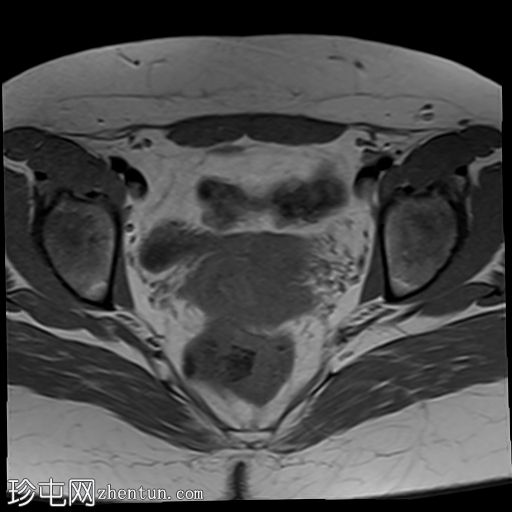

轴位

T2加权像

双侧卵巢位置接近(卵巢相吻),左侧卵巢内可见一边界清晰的囊性病变,大小约3.1 × 2.7 × 2.9 cm,T1加权像呈高信号,T2加权像可见暗点征及内部暗点征。以上MRI特征符合卵巢子宫内膜异位囊肿的诊断。

右侧卵巢可见一囊肿,大小约为 2.8 × 2.0 × 2.2 cm,T1 加权像呈高信号,囊内可见液-液平面,提示囊内含有不同时期的出血性物质。由于对侧卵巢存在典型的子宫内膜异位囊肿,且该囊肿无强化,影像学表现强烈提示为另一子宫内膜异位囊肿。

双侧卵巢囊性病变,MRI 表现符合子宫内膜异位囊肿的特征,左侧较大。未见强化壁结节或实性成分,提示无恶性转化。